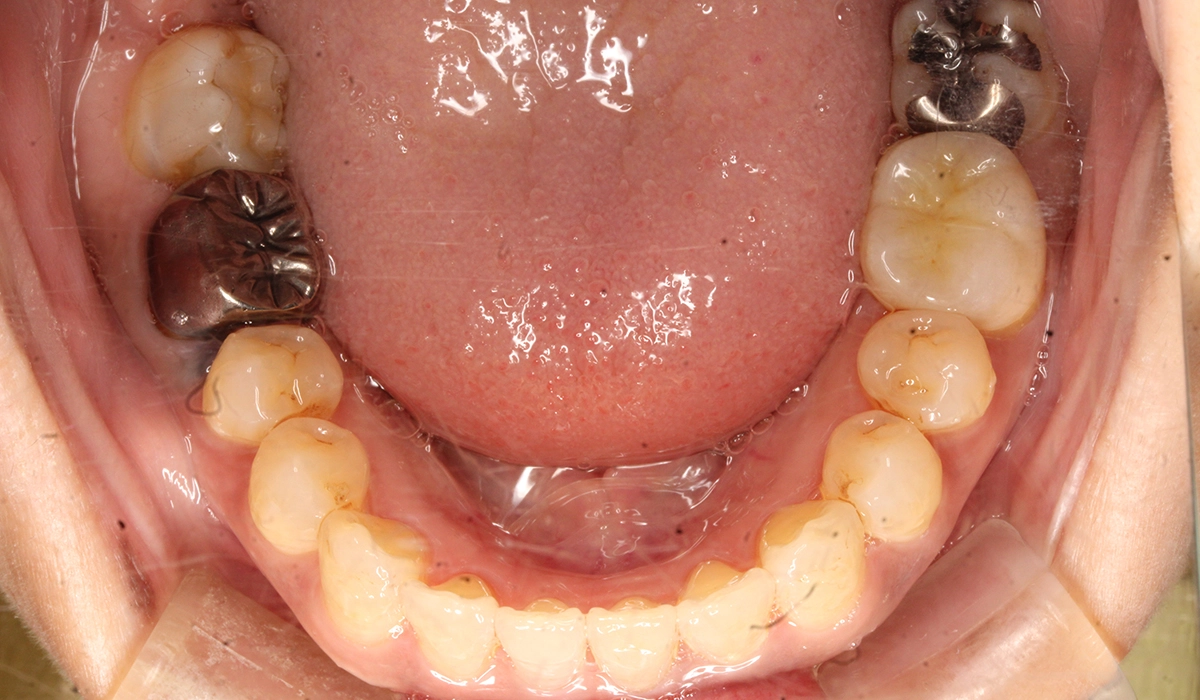

術前:下顎